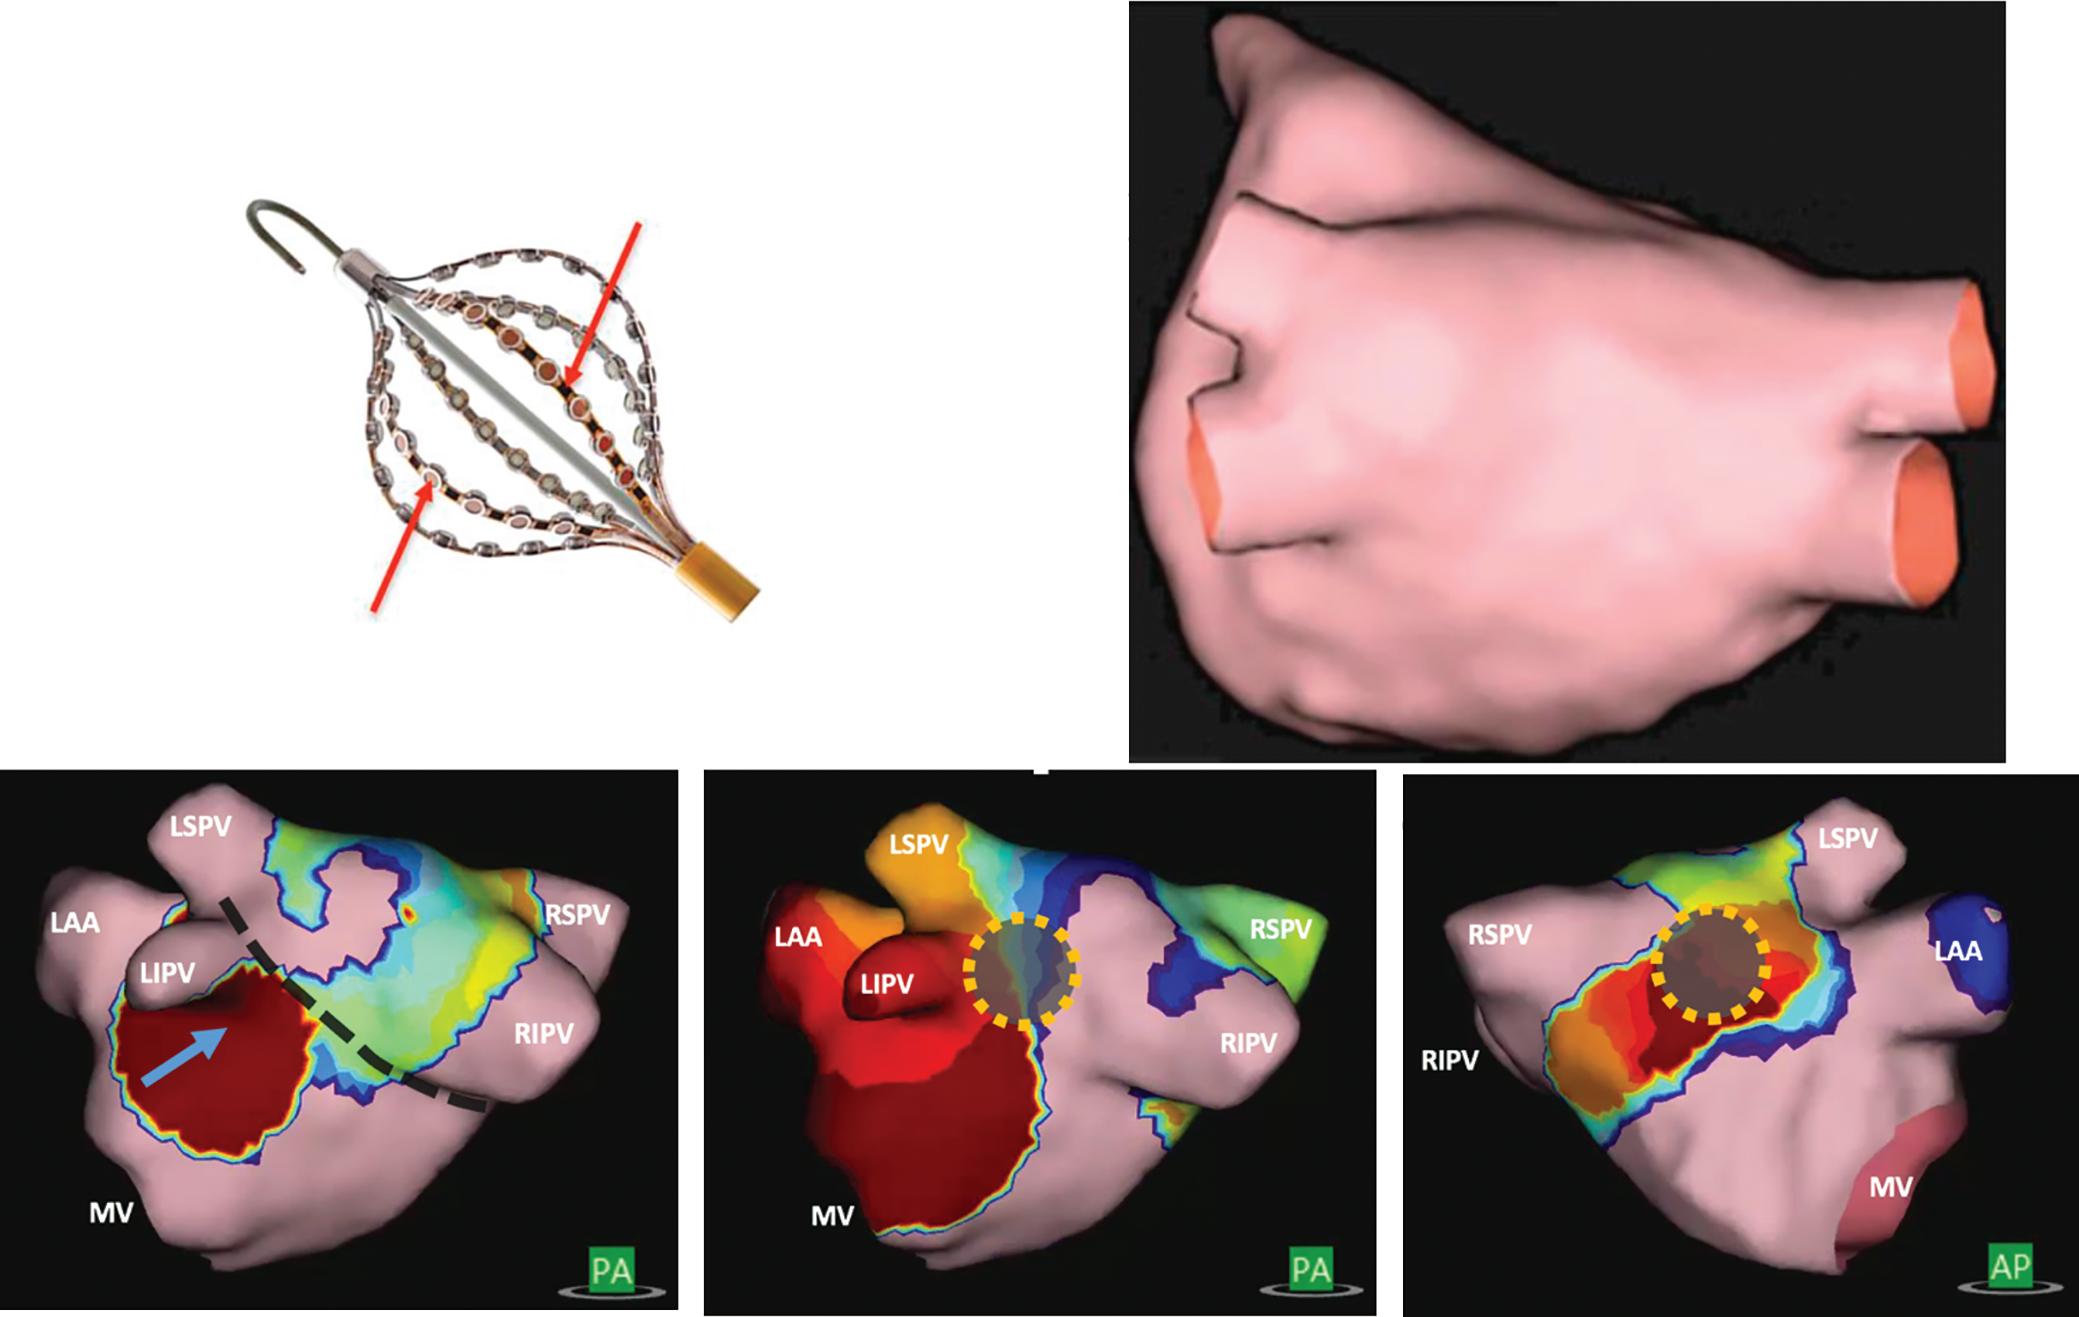

Figure 6: Ventricular Ablation Lesion Assessment

Preprocedural LGE-MRI (1 day before VT ablation)

Ablation points

Post-ablation LGE-MRI (3 months after VT ablation)

Left: 3D reconstruction of the left ventricle with LGE-based colour-coding based on thresholds for dense scar (red, >60% maximum of signal intensity) and border zone (yellow, 40–60% of maximum signal intensity), mapped using ADAS 3D. Shown are the layers at 30% of the transmurality (from endocardial to epicardial). For the post-ablation LGE-MRI (lower panel), an additional 3D reconstruction of the manually defined dark core in red (black arrow) is depicted. Blue lines indicate the plane of the short-axis slices on the right. The ablation points (TactiCath, Abbott Medical) are visualised using a 3D mapping system (EnSite Precision, Abbott Medical). Middle: Overlay of the T1-weighted short-axis slices with the colour-coding described above. The central hypoenhancement dark core of the ablation lesion is manually delineated (red border) to avoid misinterpretation as healthy tissue. Right: T1-weighted short-axis LGE-MRI slices without colour-coding. LGE = late gadolinium enhancement; VT = ventricular tachycardia.

The Dark Core Phenomenon

For image post-processing and analyses it has to be taken into account that, in contrast to atrial ablation lesions, the above-mentioned dark core phenomenon, characterised by centrally hypoenhanced lesions, has been observed even in these chronic stages of ventricular lesion formation, thus complicating the assessment of ablation-induced scarring

in the ventricle.15 As current post-processing software algorithms are solely based on hyperenhancement, hypoenhanced lesion cores are not automatically identified and thus have to be delineated manually to avoid misinterpretation (Figure 6).

While Vunnam et al. have recently reported to have found ‘dark core’ lesions only up to 1 month after RF ablation but not at later stages, which is in line with previous preclinical and clinical data, Dabbagh et al. consistently observed lesions with hypoenhanced cores as late as 30 months post-ablation in all patients after repeat ablation of post-MI substrates.11 15 16 63

Of note, at our centre, we encounter centrally hypoenhanced lesions in around 60% of the patients at the systematic follow-up LGE-MRI 3–6 months post-VT ablation. Interestingly, in the study of Vunnam et al., comparison with pre-procedural LGE-MRI scans revealed that dark core lesions could only be observed in previously non-fibrotic myocardium without preexisting scar, suggesting that different wash-in/ washout kinetics in scarred versus non-scarred myocardium play a role in this context. This is in line with a study in patients devoid of structural heart disease in whom LGE-MRI was performed at a mean of 22 months after ablation of idiopathic VT, where no central hypoenhancement of lesions was encountered.16